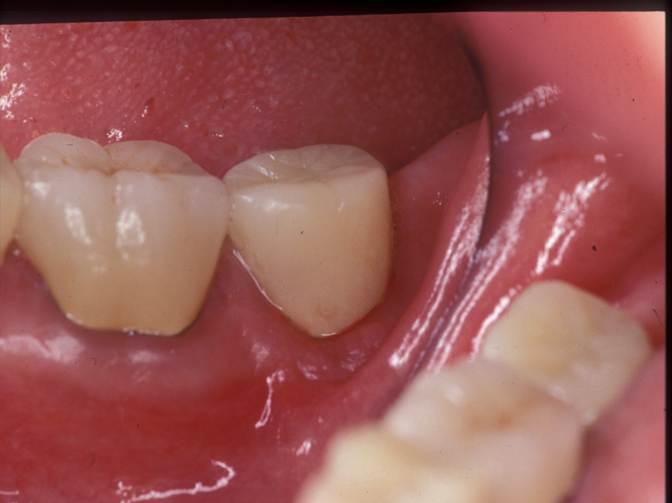

術前写真です。

2回、薬を交換して3週間後です。

綺麗な色になりました。神経を取った後の歯は、裏側から漂白できます。表側のエナメル質が綺麗に残っていて、エナメル質の裏側の象牙質が変色しているためです。